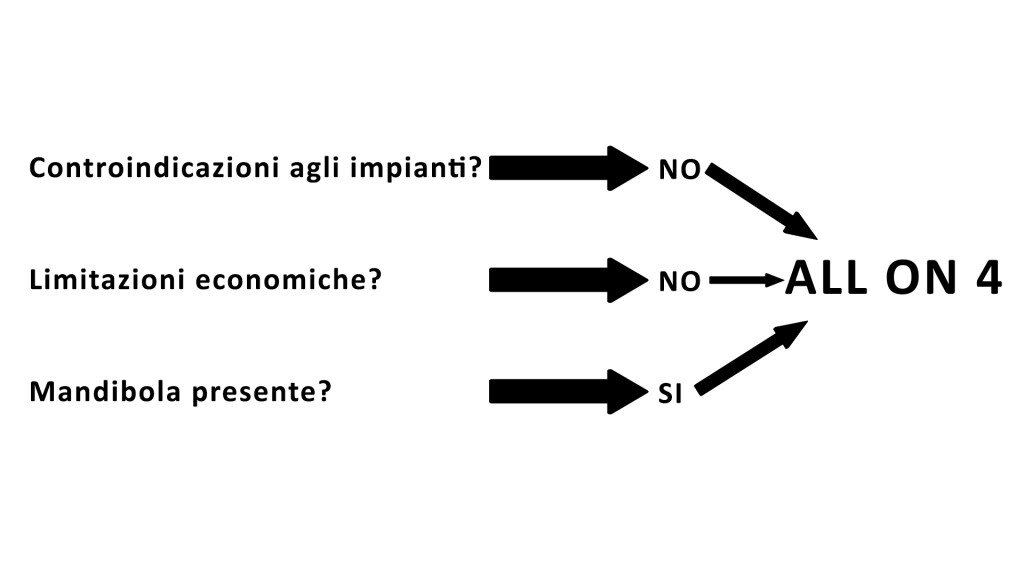

La mia valutazione fu semplice, veloce, direi praticamente immediata.

“All-on-4 sopra e sotto” dissi a Lorena, la segretaria che seguiva la visita.

Se hai compreso quanto ho provato a spiegare sopra, saprai come ho fatto a risolvere nella mia testa il caso di cui parlavamo (ed eccoci finalmente ai due segreti):

1) Ho spento (in realtà ho lasciato spento) il cervello e

2) Ho seguito pedissequamente il protocollo decisionale per questi casi

Zero seghe mentali.